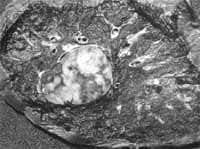

Figura 3. Patología macroscópica de tumor carcinoide endobronquial típico de localización central.

Variando de manera importante las características de cada uno (5).

Los tumores centrales usualmente se localizan en los bronquios fuente o lobares, tienen características pedunculada y friables que puede ocluir totalmente o no la luz bronquial, al corte se encuentra una masa de color nácar con focos hemorrágicos (2,16). Si se encuentran focos de osificación el tumor se torna duro y áspero en las zonas donde se localizan dichos tejidos (2).

Figura 6. Patología macroscópica tumor carcinoide bronquial atípico de localización periférica

Cortesía Dra. Paulina Ojeda, Patóloga, Hospital Santa Clara E.S.E.

Algunos autores han sugerido que los carcinoides atípicos son en su gran mayoría de localización periférica, sin embargo, esta observación no ha sido conclusiva en todos los estudios; lo que si se ha observado es que el tamaño del tumor es mayor, teniendo un diámetro mayor (3.6 cms) que el de los carcinoides típicos (3), de igual forma aunque pueden ser bien delimitados puede desarrollarse infiltración tumoral al parénquima pulmonar subyacente (1).